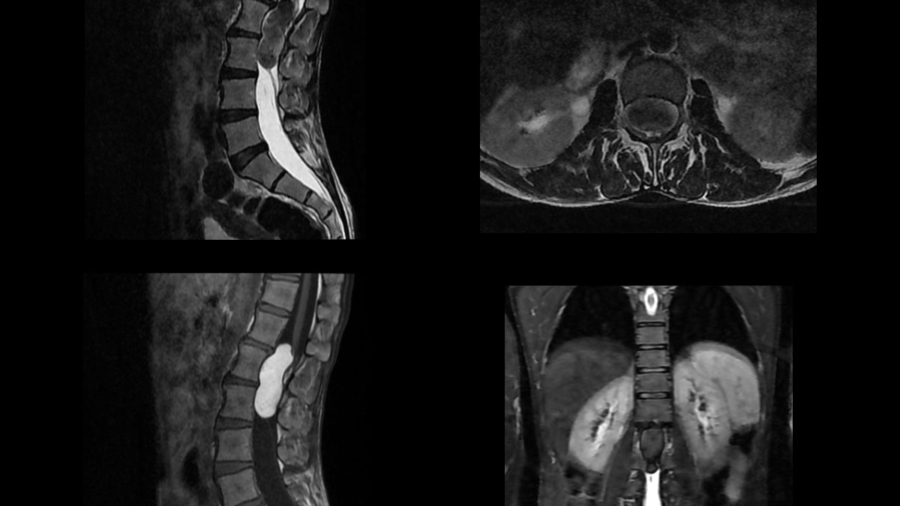

45 YEAR OLD MALE, Presenting compaints: Patient presented with lower back pain since 5 years; right leg numbness and tingling since 6 months and acute onset urinary incontinence